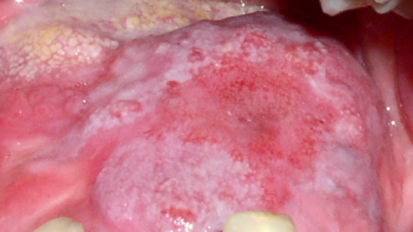

El láser en la odontología pública

El Dr. David Montero dictó una ponencia de cuatro horas en el Congreso Odontológico Internacional de Atención Primaria y ...